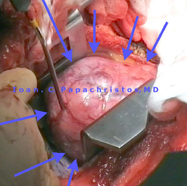

ΦΩΤΟΓΡ. 7-8: Διφασικό Θύμωμα 9,5 x 8 x 7 cm σε 62-χρονη μη-καπνίστρια, σε επαφή με Άνω Κοίλη Φλέβα & Δεξιό Κόλπο καρδίας (δεξιά θωρακοτομή δια κοίτης 4ης πλευράς ή 3ου μεσοδιαστήματος).